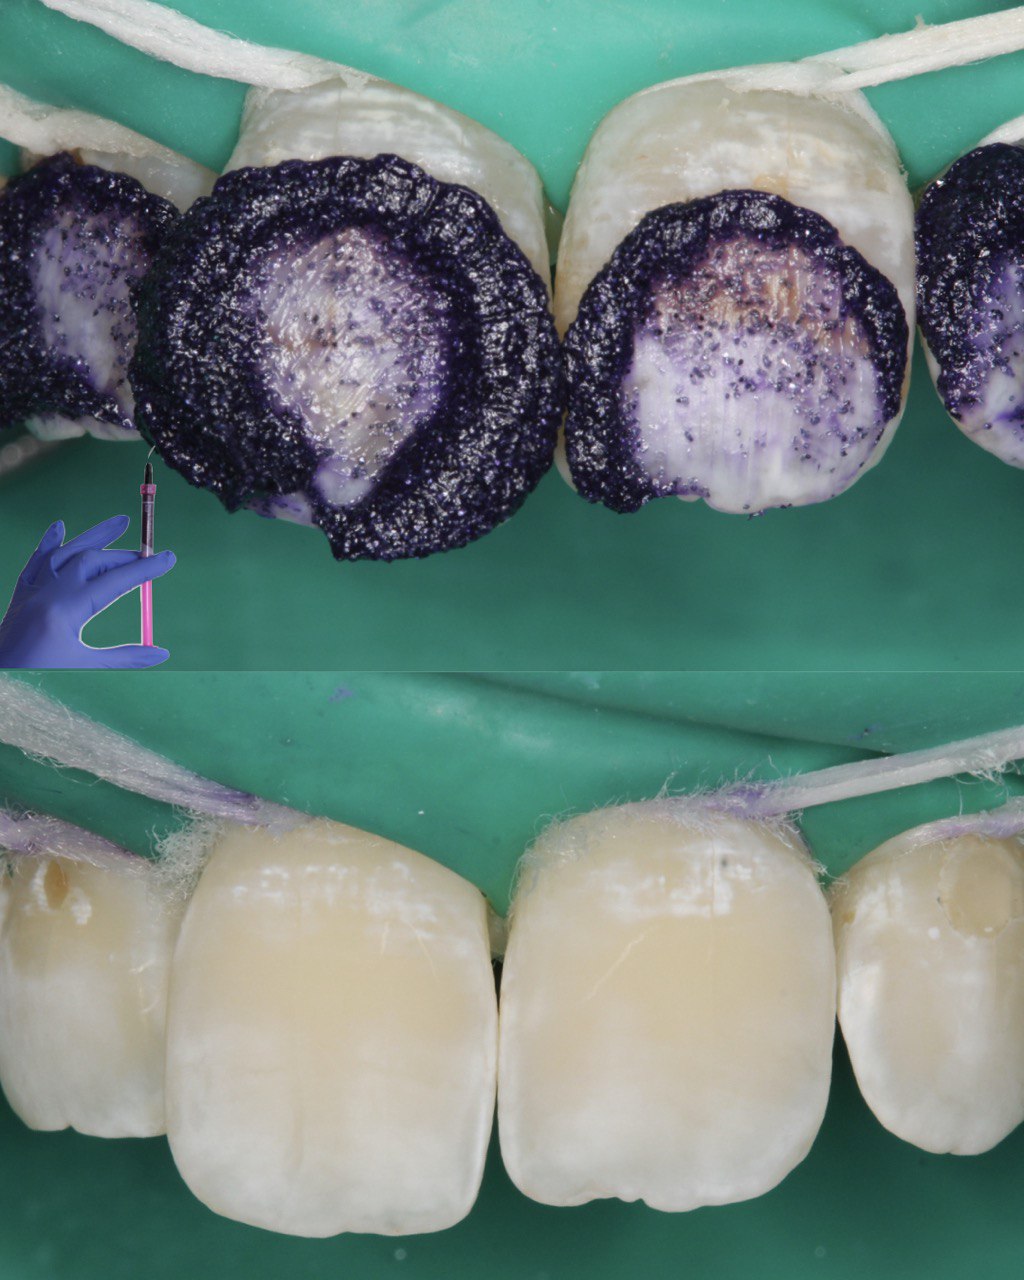

Опис ситуації : Пацієнт звернувся для планового огляду та професійної чистки. При візуальному огляді наліт може здаватися незначним, проте для детальної діагностики ми використовуємо спеціальний індикатор.

Що ми зробили? Етап індикації:

Ми нанесли спеціальний гель-індикатор, який фарбує наліт у різні кольори:

Рожевий/Червоний: Свіжий наліт (до 24 годин).

Синій/Фіолетовий: Старий, зрілий наліт (понад 48 годин), який є найбільш небезпечним для емалі та ясен.

Аналіз: Фото чітко показує зони, де пацієнт пропускає очищення під час домашньої гігієни (особливо пришийкова ділянка та міжзубні проміжки).

Результат та рекомендації Проведено професійну гігієну (Air-Flow + полірування). Підібрано індивідуальні засоби догляду (щітка, монопучок, флосс). Проведено урок гігієни: пацієнт побачив свої “слабкі зони” та навчився вичищати їх правильно.